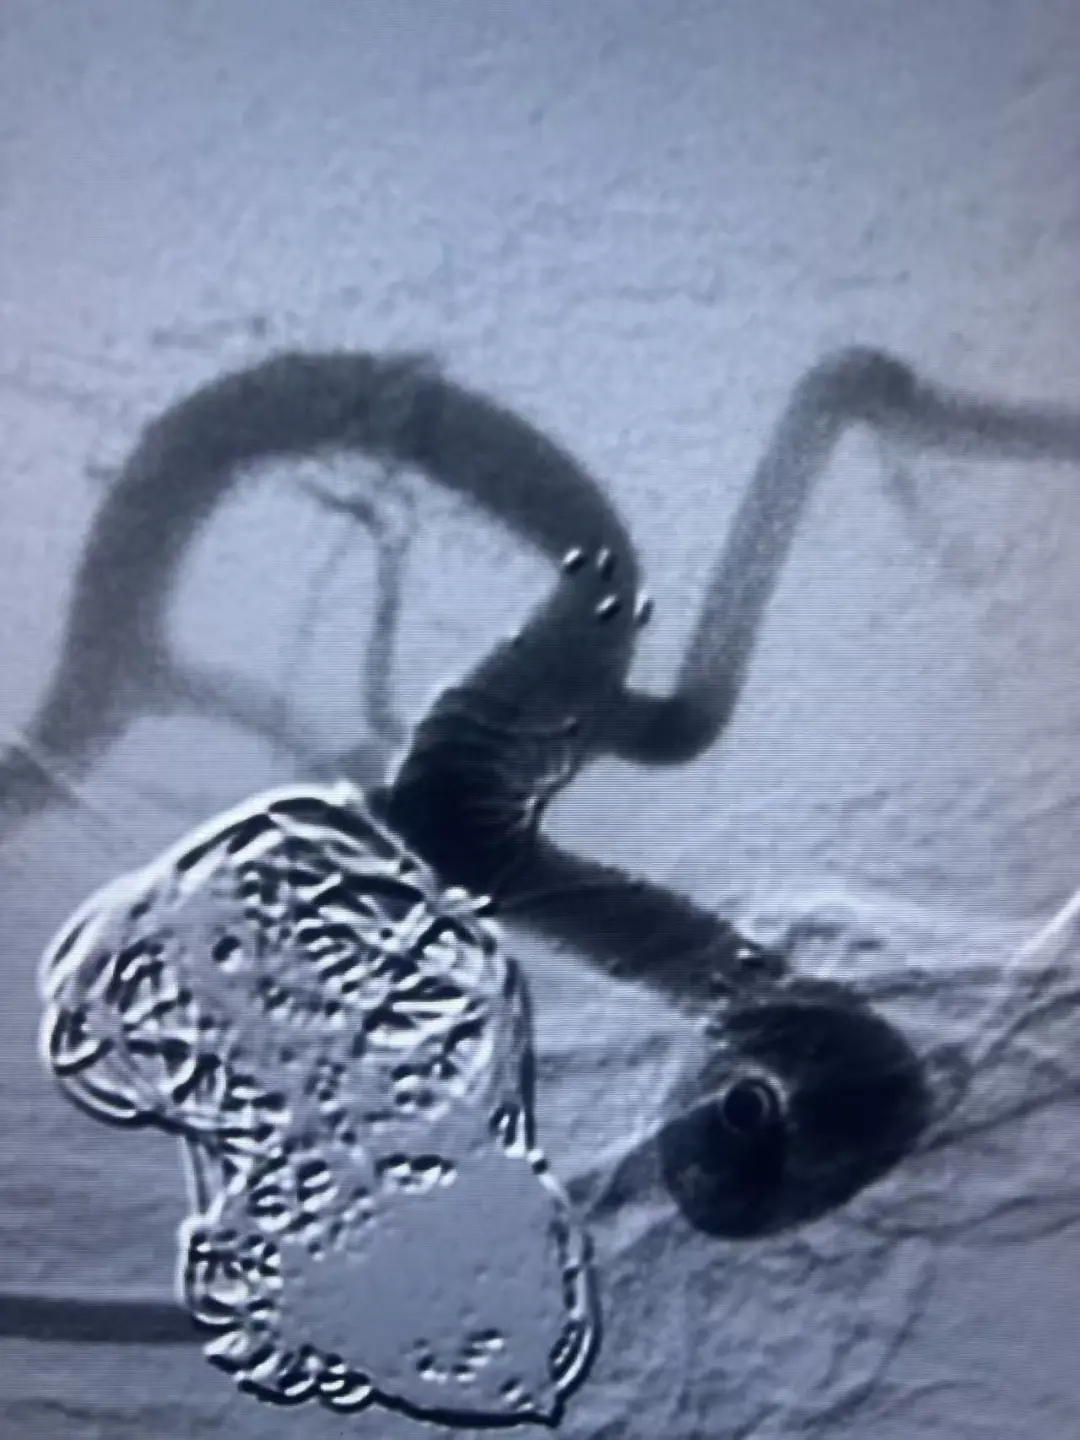

手术在全身麻醉下进行。医生成功穿刺右侧桡动脉,精准植入密网支架。整个过程非常顺利,支架位置理想,完美覆盖动脉瘤并保护了正常血管分支。

术后影像显示,动脉瘤内血流明显受阻,手术效果立竿见影。患者恢复良好,具体表现为:无任何神经系统并发症; 穿刺部位无异常;术后24小时即可正常活动。